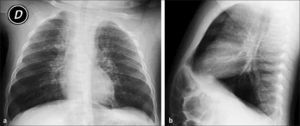

Este compromiso se observa en Rx simple como aparición de opacidades peribronquiales que adoptan un aspecto radiado desde el hilio pulmonar hacia la periferia; la medida que estos cambios progresan, el patrón se hace más confluente. La presencia de edema e infiltrados celulares en los espacios peribronquiales produce disminución de calibre y obstrucción de la vía aérea, lo que determina aparición de dos hallazgos importantes que habitualmente se asocian a la neumopatía intersticial: hiperinsuflación y atelectasias (1).

La hiperinsuflación es consecuencia del mecanismo de válvula que se produce en espiración en la vía aérea inflamada, hecho que se acentúa en la edad pediátrica por su escaso calibre, generando atrapamiento aéreo con aumento de la transparencia del parénquima pulmonar. La proyección lateral es de gran utilidad para valorar el aumento del diámetro antero-posterior, aplanamiento diafragmático y aumento de transparencia del espacio retroesternal, como signos de hiperinsuflación (Figura 7). En los niños es frecuente observar atelectasias, especialmente subsegmentarias, por el menor desarrollo de la ventilación colateral en el pulmón infantil (canales de Lambert y poros de Kohn). Estas atelectasias aparecen como bandas lineales, densas, pequeñas, de contornos bien definidos, visibles especialmente en las regiones medias inferiores de los pulmones. En niños mayores es posible observar también atelectasias segmentarias o lobares, con un patrón anatómico similar al que se observa en adultos (4).